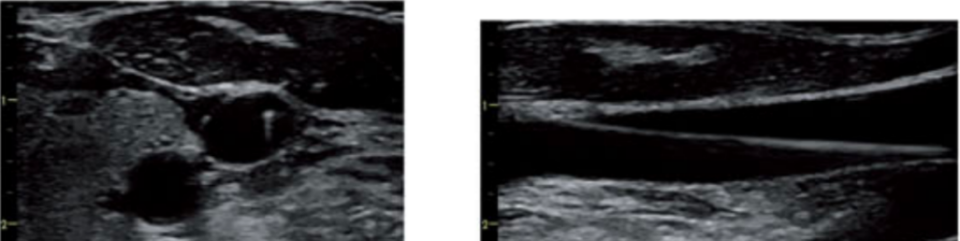

第二步 判断静脉是否通畅

通过轻压探头的手法来了解静脉能否完全被压闭,同时使用彩色多普勒成像和频谱多普勒测量来再次确认静脉的通畅性,排除静脉血栓,并量化血流量。